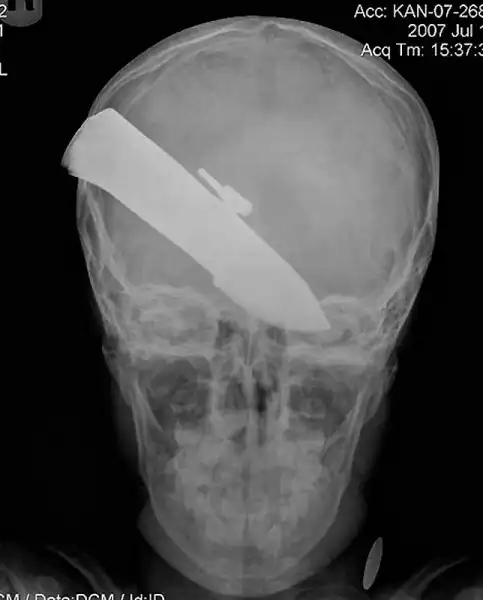

Нож в голове 10-летнего мальчика. Мальчик выжил.

12-сантиметровый нож в черепе подростка.